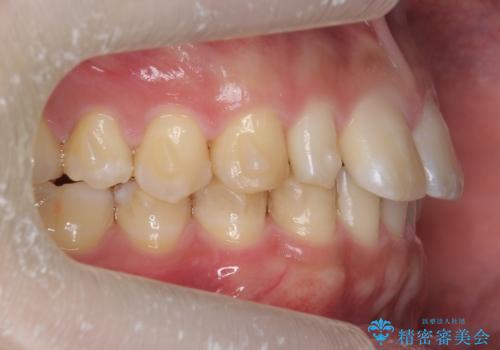

前歯のすき間 小さい歯がある 前歯の並びをきれいにしたい

- 前歯のすき間を気にして来院。

前から2番目の歯が小さく厚みがあったため(矮小歯)

矯正治療で1番目の歯を寄せて2番目の歯はセラミックで形をととのえています。